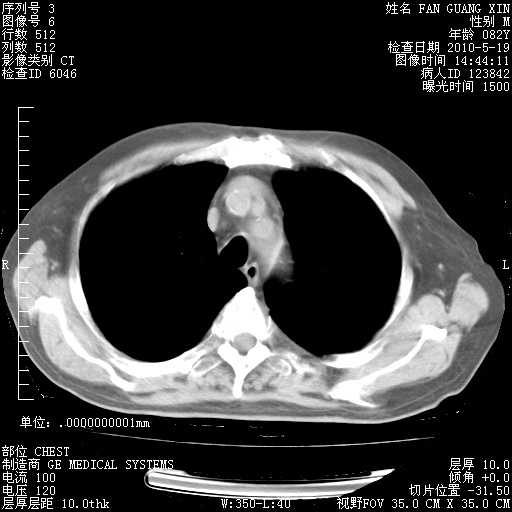

复查肺部CT,明显好转。为什么发热呢?

治疗3周后的肺部CT

治疗3周后的肺部CT纵隔窗